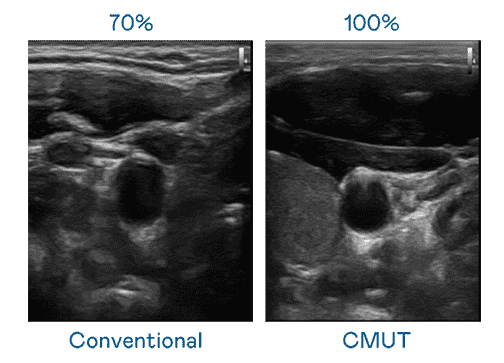

CMUT 技术是一种用电容式微机电元件来产生超音波讯号的技术。。与传统 PZT 压电式技术相比,,,CMUT 频宽增加 30%,,,,更宽频的超音波讯号让影像解析度大幅提升,,是实现高影像品质医疗超音波扫描、、、促进精准医疗发展的关键技术。。

大频宽带来超清晰影像

超音波影像的解析度高低,,,,首先取决于探头能发出的讯号频宽。。。。壹号平台 CMUT 可提供高清晰的超音波讯号,,,,提供高频宽、、、高灵敏度、、、影像纹理细节更高的超音波影像,,,协助医护人员缩短影像判读时间及利用精准的医疗影像进行诊断。。。。